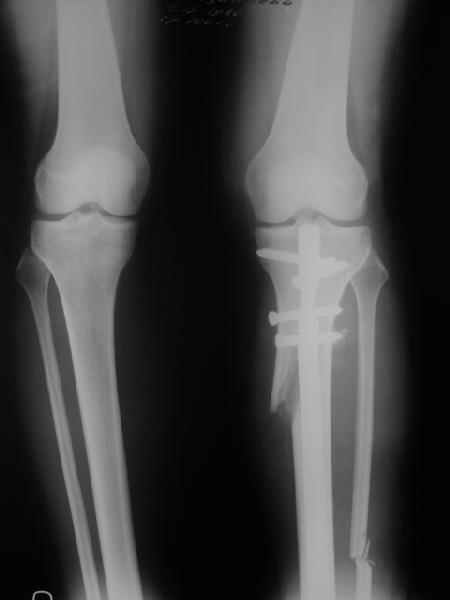

Как уже писал, вчера сделал одну ногу (может, свой плюс будет что не обе- вдвое меньше травма, сразу на костыли встанет, оперированную ножку немного разомнет, тут и вторую заделаем).

Операция была интересной, много полезного опыта приобрел.

Снимки в приложении - фас сравнительный с неоперированной ногой. Жду критики.

Впрос про остеотомию большеберцовой непраздный. Эта получилась при надломе несколько более наклонно, чем я делал (сейчас проблема,

как на второй ноге сделать так же). Вот этот высоящий "зуб" центрального отломка не заменит ли в плане косметики то, что получается при медиализации дистального?

Nice job!

It is very interesting to me that as you have derotated the tibia you have centred the patella, I think and the prox tibia looks much more anatomic.

The analysis in the attached images is direct, just using the tools.

Tibial tilt is perhaps more than you want but the tibial correction is to 90 (very slight over

correction.

Will need full length views to tell us about the hka but it appears neutral.

Measurements took 4 mins

Derek